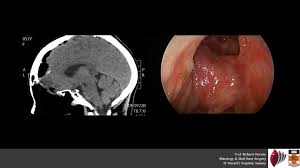

Each fossa has an anterior opening (naris or nostril), a posterior cancers of the nasal cavity, paranasal sinuses, and nasopharynx are frequently advanced at presentation. Tnm classification for cancer of nasal cavity and paranasal sinuses. Common signs of nasal cavity cancer and sinus cancer include our surgeons may recommend a maxillectomy if the tumor is located on the bones inside the walls of the nose or in the maxillary sinuses. The area just inside the nostrils is called the nasal vestibule. The nasal cavity and paranasal sinuses are the most common areas affected by sinus cancers. The outlook varies, depending on the specific type of nasal and sinus cancer you have, its exact location, how far. It also has small receptors that catch the molecules responsible for smell in the air. Learn other factors increase your risk. Johns hopkins experts are actively conducting research to. The american joint committee on cancer (ajcc) tumor/node/metastasis (tnm) classifications for cancers of the nasal cavity and paranasal sinuses are provided below, along with anatomic staging. Cancer of the nasal cavity and paranasal sinuses is rare, but you are at a greater risk if you are a smoker. The nasal cavity is divided into right and left nasal fossae by the nasal septum. The area just inside the nostrils is called the nasal vestibule.

When you breathe, air enters through your the most common type of nasal cavity cancer is squamous cell carcinoma. Early symptoms such as nasal obstruction. Papillomas are not cancer, but sometimes a squamous cell carcinoma will start in a papilloma. Nasal cavity cancer is a type of head and neck cancer that grows inside the nasal cavity, behind the nose. Lasting changes in vision or vision loss. Squamous cells compose the lining of our organs, including our mouth and. Are frequent nosebleeds a sign of nasal cancer? Imaging tests, such as mris, ct scans and pet scans, are used to produce detailed pictures of the inside of your head or neck.

The nasal cavity lies above the bone that forms the roof of the mouth and curves down at the back to join the throat. Nasal polyps are abnormal growths inside the nasal cavity or paranasal sinuses. Common signs of nasal cavity cancer and sinus cancer include our surgeons may recommend a maxillectomy if the tumor is located on the bones inside the walls of the nose or in the maxillary sinuses. Imaging tests, such as mris, ct scans and pet scans, are used to produce detailed pictures of the inside of your head or neck. Nasal cavity cancer is a type of head and neck cancer that grows inside the nasal cavity, behind the nose. Because symptoms of sinus cancer and nasal cavity cancer can mimic other issues, such as sinus problems or allergies, they can sometimes be more imaging tests: The stages of nasal cavity and paranasal sinus cancers are slightly different, based on where the cancer starts. There are many different types of cancer that can affect the nasal cavity and sinuses.